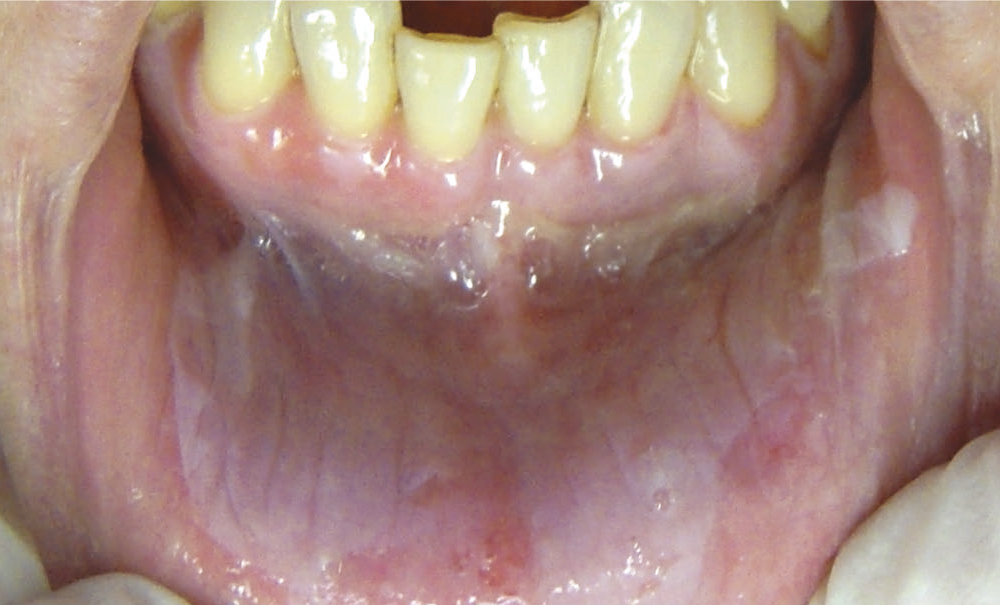

L’examen endobuccal de la mère (fig. 1) a permis de mettre en évidence un plancher buccal jaunâtre avec présence de plages érythémateuses et de lésions érosives de 5 à 8 mm de diamètre. À la palpation…